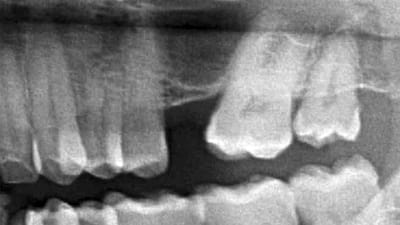

Online Only Implantology Online Only Is Residual Bone Height an Absolute Indicator for Simultaneous Implant Placement in Lateral Wall Sinus Grafting By Gregori M. Kurtzman, DDS, Lanka Mahesh, BDS May 01, 2017 10 min read